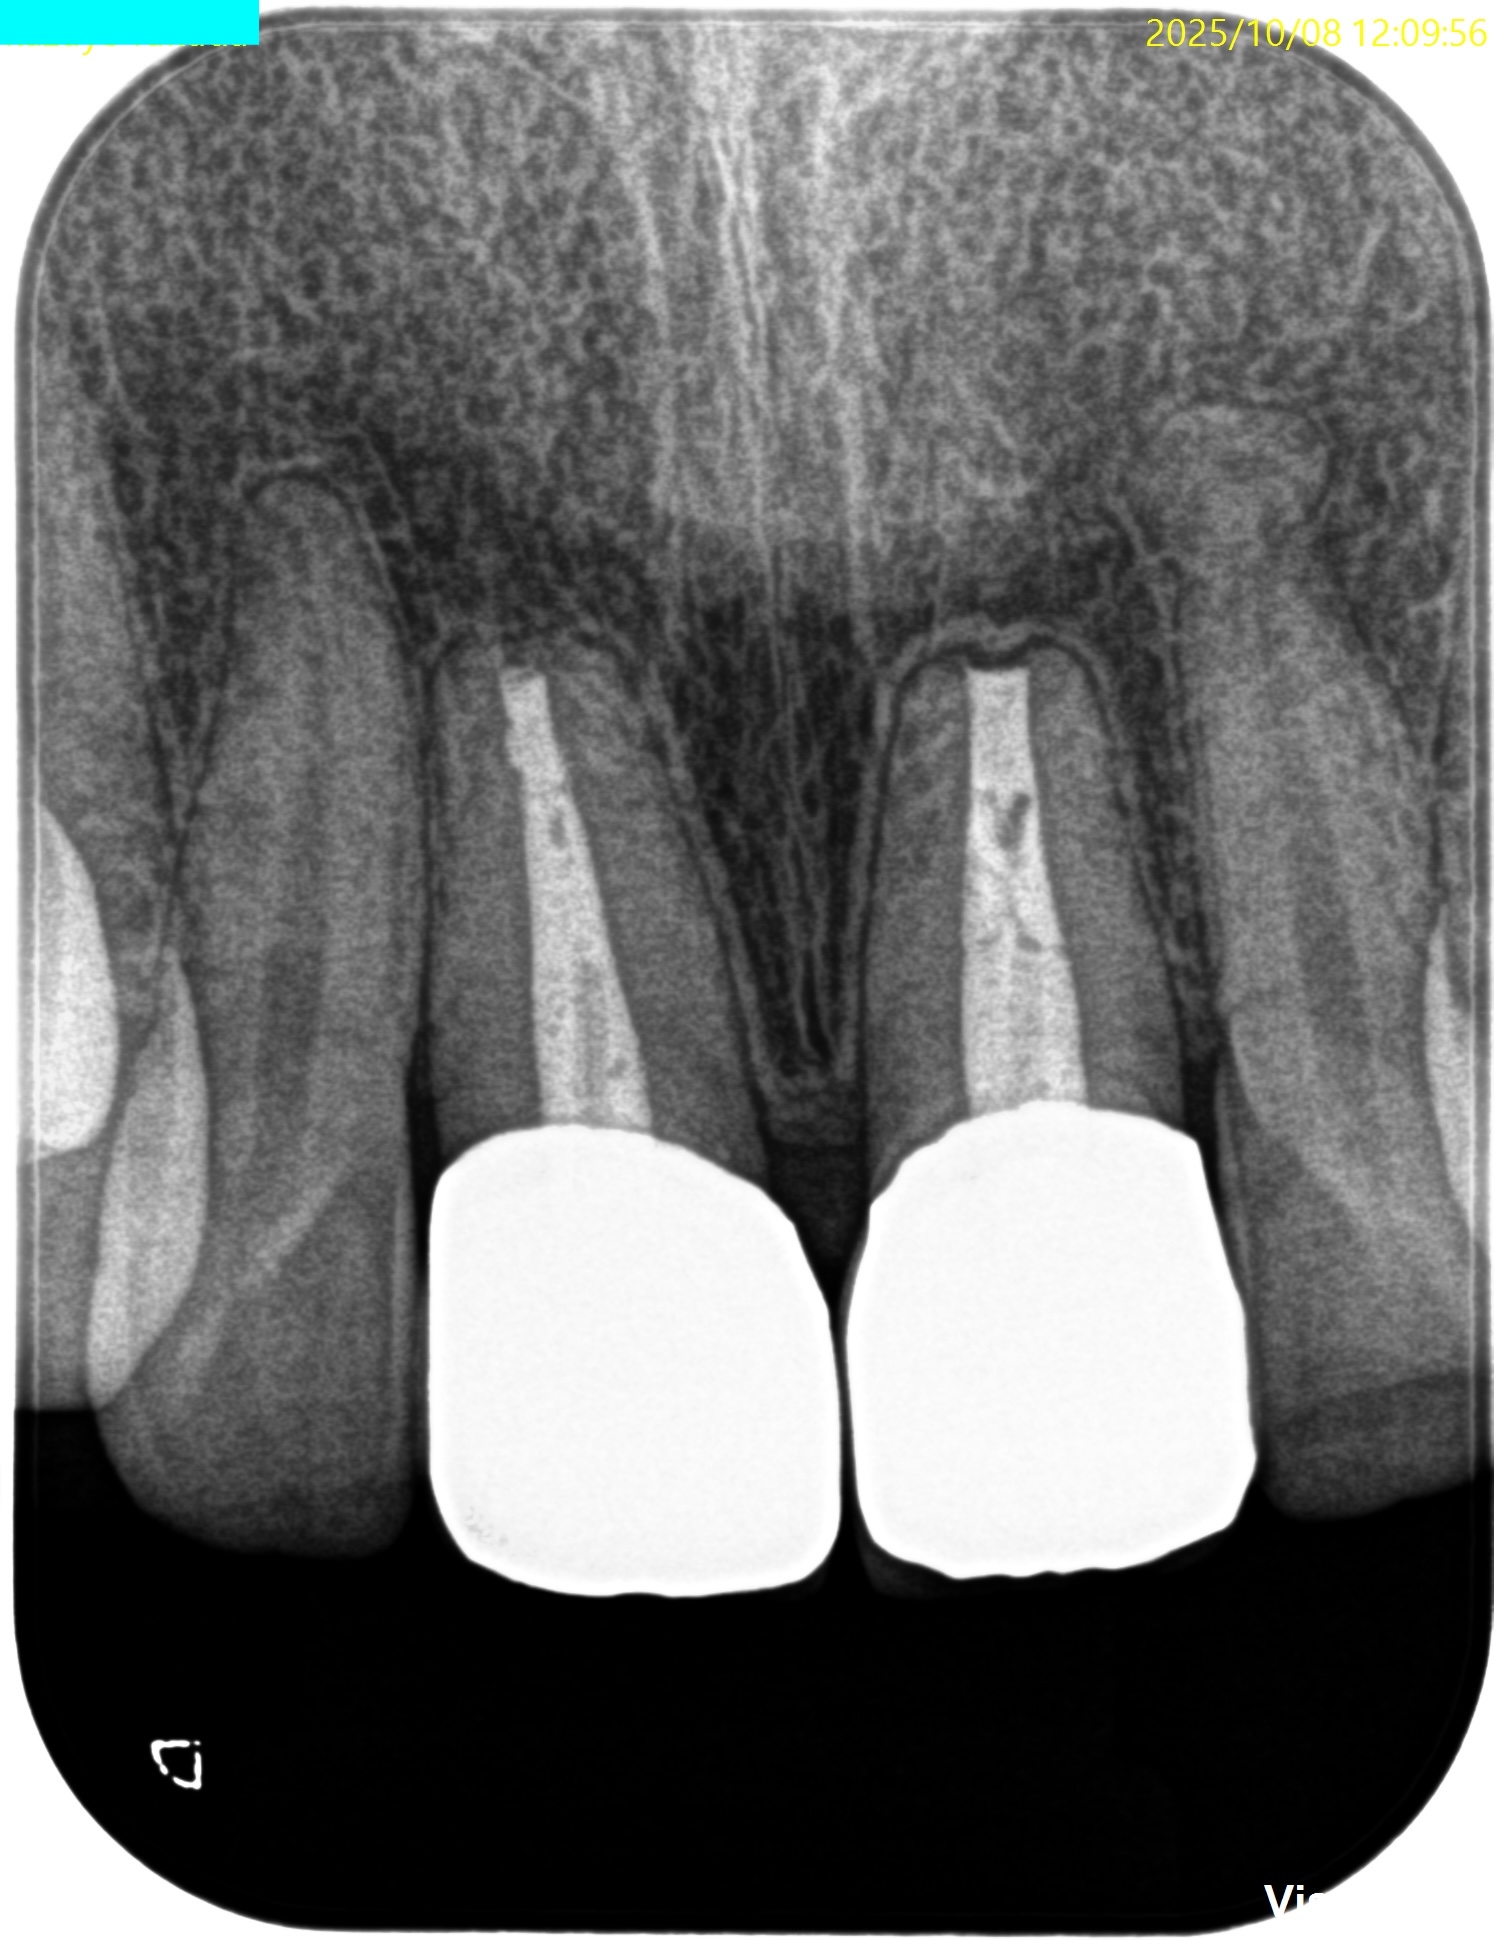

#8,9 Apicoectomy 1yr recall(2025.10.8)

#8

#9

術後と比較した。

術前の問題は消失した。

#9はやはり術前の予想通り1mmの切断で事足りた。